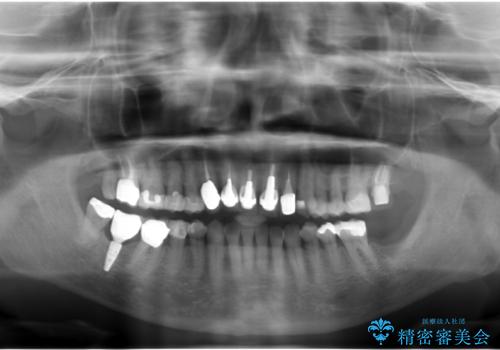

60代女性 奥歯のインプラント

- 60代女性

- 右下の歯を抜いた箇所に親知らずを矯正治療で移動できないかというご相談で来院。

親知らずを一本分前には基本的には難しいという説明をしました。

また、受け口のかみ合わせのため、下の親知らずは上の7番目の歯に咬合して機能しているため、そのままの位置の方が良さそうでした。

欠損の部分にはブリッジまたはインプラント、義歯の選択肢がありますが、インプラント治療をご希望されました。

他院で抜歯後いらしたため、骨ができるのを待って、オペは2回法で行っております。

2回法の利点は、骨増成が確実であることと、FGGが可能で長期に安定した歯ぐきが得られることです。